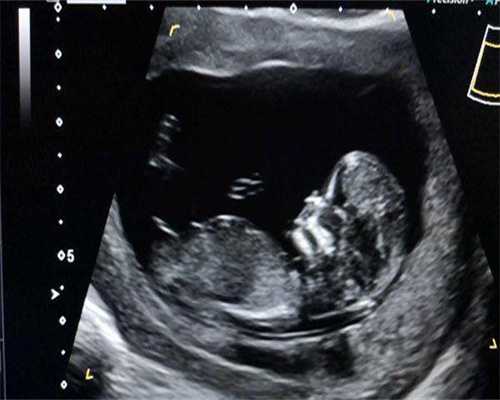

在试管促排卵期间,还会定期进行超声波检查和血液检查,以确定最佳排卵时间。一旦监测结果显示卵泡已经成熟,可以受精,医生就会安排促排卵手术,并将受精卵移植回 子宫。

在试管促排卵前,医生还会进行详细的评估,包括检查子宫内膜和黄体的发育情况。通过定期超声波检查和血液化验监测排卵过程,并确定最佳受孕时间。

在监测排卵期间,医生会进行多次超声波检查和血液化验,以确定卵泡发育情况和黄体引入情况。这有助于确定最佳受孕时间。